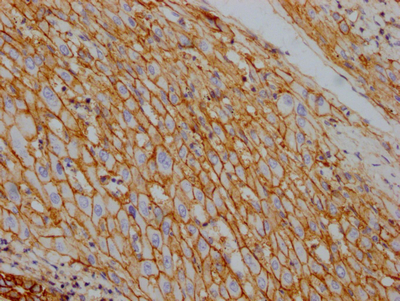

IHC image of CSB-RA796310A0HU diluted at 1:100 and staining in paraffin-embedded human liver cancer performed on a Leica BondTM system. After dewaxing and hydration, antigen retrieval was mediated by high pressure in a citrate buffer (pH 6.0). Section was blocked with 10% normal goat serum 30min at RT. Then primary antibody (1% BSA) was incubated at 4℃ overnight. The primary is detected by a Goat anti-rabbit IgG polymer labeled by HRP and visualized using 0.05% DAB.